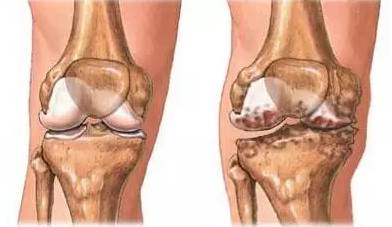

△ 左侧:健康的膝关节,右侧:存在软骨磨损、骨刺、关节退行性变的膝关节

“骨刺”也叫骨质增生,而在医学中其真正的术语是“骨疣”,这是关节因种种原因造成软骨的磨损、破坏,并促成骨头本身的修补、硬化与增生。

骨刺像脸会长皱纹、人体会衰老一样,是一种自然的老化现象,并不是疾病。

骨刺是骨骼的修理工

骨刺就是这个机制中的成员,是人体为适应力的变化而产生的一种自我保护反应。可以说,骨刺是骨骼的修理工。